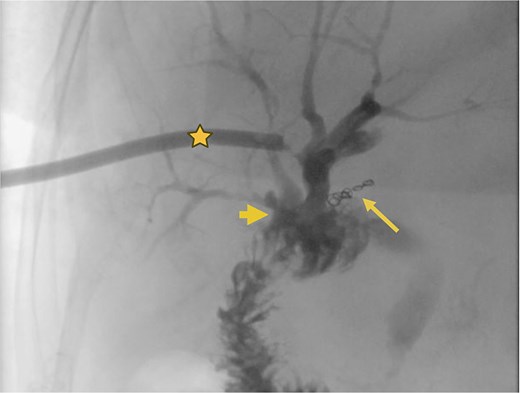

Surgical reconstruction revealed an excluded PRHD and ARHD–LHD continuity with obstruction 10 mm from the confluence. The PRHD catheter was found outside the biliary tract, so a transhepatic Nelaton catheter was placed from inside to out. A neoconfluence of PRHD with ARHD and LHD was created with a 30 mm hepaticojejunostomy. A transanastomotic Nelaton catheter and a supranastomotic ARHD catheter were left in place. Estimated blood loss: 300 cc. In the immediate postoperative period, the patient developed melena and bleeding from the Penrose drain. Cholangiography via the right percutaneous catheter showed no contrast leakage. Angio-CT revealed an 8 × 5 mm saccular lesion in the anterior right hepatic artery (Segment V), consistent with a pseudoaneurysm (Figs 1 and 2). Selective embolization with three microcoils (2 × 3 × 2.3 mm) was successfully performed (Fig. 3). The patient had a favorable recovery, with no further bleeding, and was discharged in stable condition for outpatient follow-up. Control imaging of the ARHD catheter confirmed adequate visualization of all hepatic ducts, allowing catheter removal (Fig. 4).

Supranastomotic percutaneous transcatheter cholangiography. Hepaticojejunostomy (arrowhead), microcoils (arrow), and percutaneous catheter (star).